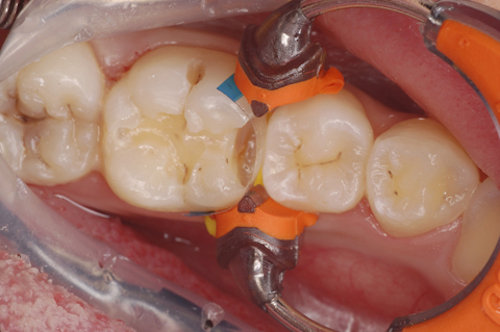

ダイレクトボンディング

むし歯を削ってコンポジットレジンという材料で修復する治療です。